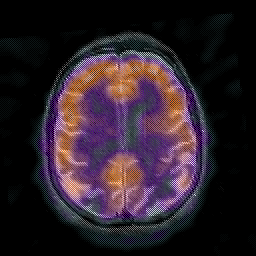

Alzheimer's disease: overlay -- Slice #35

[Home][Help][Clinical] Slice 35